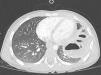

Niño de 3 años, valorado en urgencias por fiebre y tos de una semana de evolución, con buen estado general. A la auscultación pulmonar destacaba hipoventilación y crepitantes en base izquierda, mostrando la radiografía de tórax aumento de densidad en lóbulo inferior izquierdo con imágenes hidroaéreas en su interior y pinzamiento del seno costo-diafragmático ipsilateral (fig. 1). El paciente no disponía de radiografías previas; se planteó diagnóstico diferencial entre neumonía complicada con necrosis y derrame paraneumónico versus hernia diafragmática congénita con contenido intestinal en tórax. Se solicitó tomografía computarizada torácica, que demostró integridad diafragmática, identificando imagen compatible con neumonía cavitada sin derrame pleural (fig. 2). Tras antibioterapia endovenosa con cefotaxima y clindamicina presentó normalización radiológica a los 2 meses del alta (fig. 3).